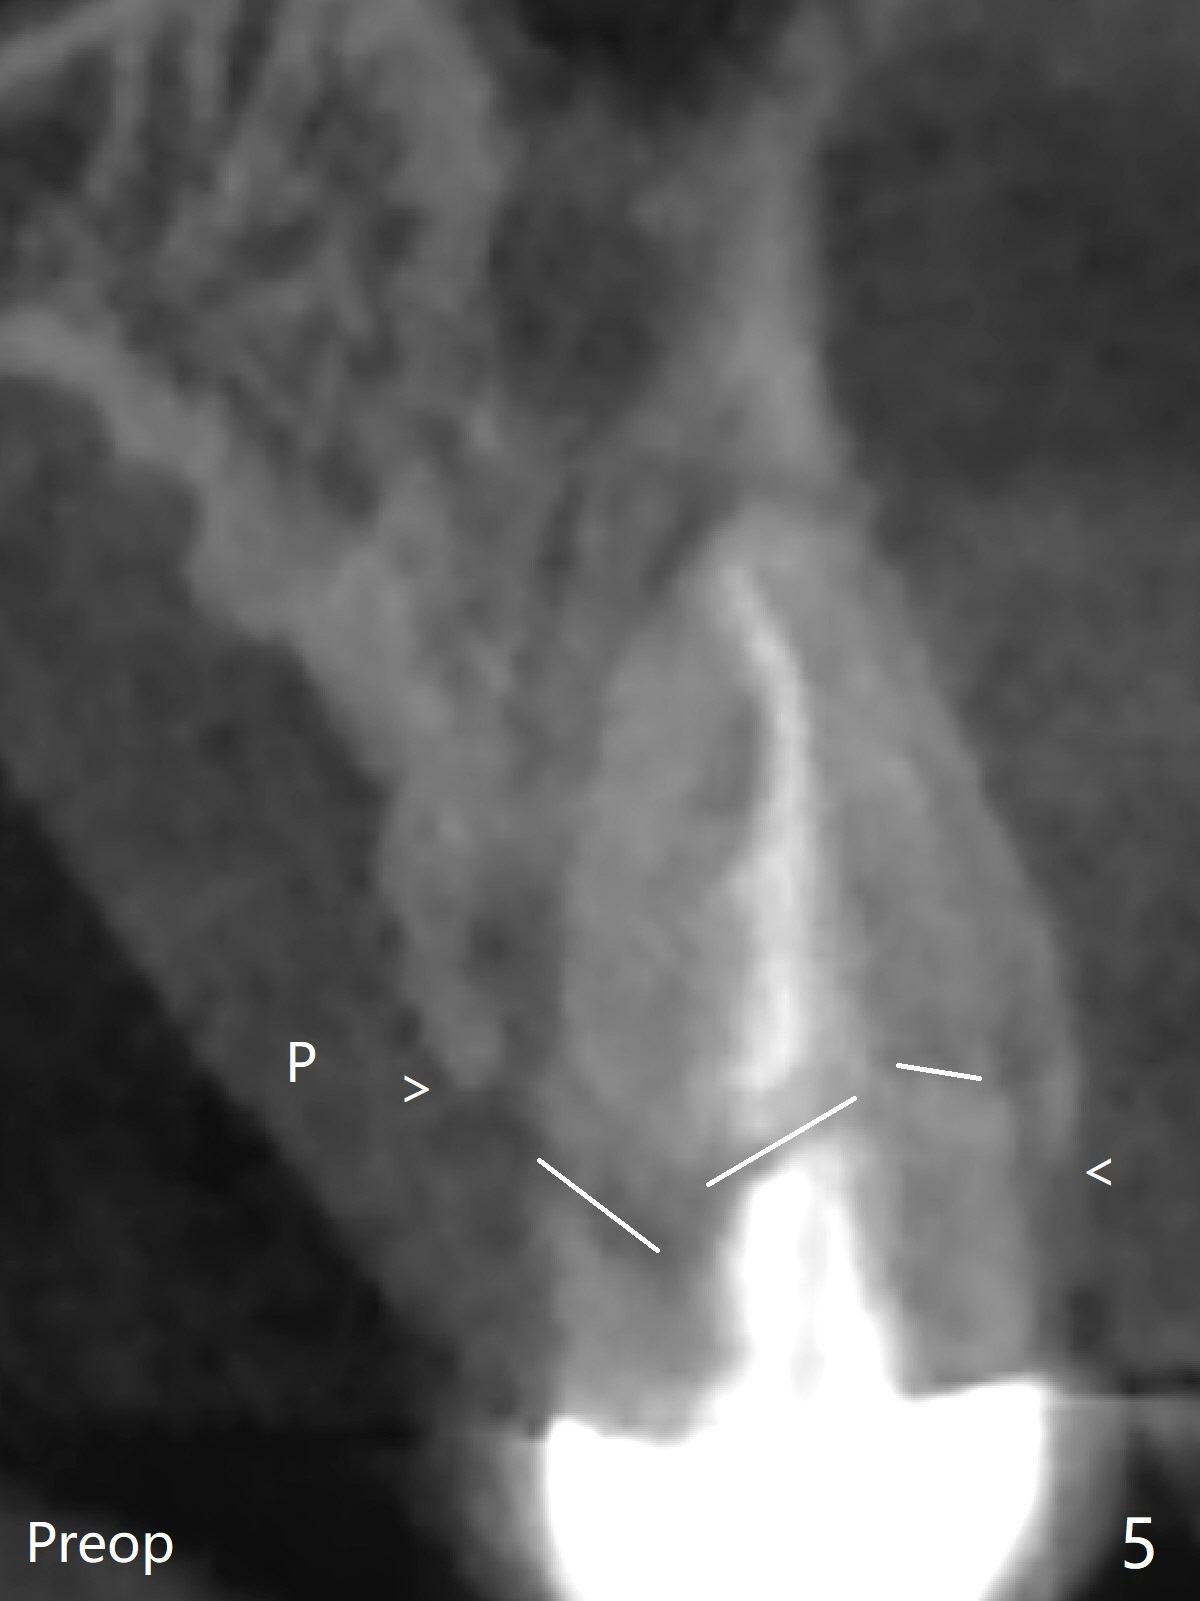

DIO lab refuses fabricating guide because of the large socket and recommends extraction and socket preservation at #13. Due to short apical bone (Fig.5,7), a long dummy implant (3.8x15 mm) is placed with periimplant space immediately post extraction (Fig.1 *). The final implant is larger (4.5x15 mm) with simultaneous sinus lift and periimplant bone graft (Fig.2,6,8 *). To repair the palatal crest defect (Fig.3 *) associated with tooth fracture (Fig.5 white dashed line), the implant is not placed too palatal with sufficient amount of the bone graft (Fig.4,6 *). The native bone (higher in bone density, Fig.9 white arrowheads, as compared to black one (for bone graft)) appears to have grown into the space between implant threads 5.5 months postop. The permanent crown/abutment is loose 1 year 9 months post cementation; after proximal reduction (Fig.10 arrowheads), the abutment is reseated completely. Pick up impression is taken and a healing abutment is placed. A few days later, the crown and abutment (separate) are seated passively; the abutment screw is retightened; the crown is re-cemented. The crown and abutment is removed for residual cement removal (Fig.11). Since there is mild buccal plate atrophy (Fig.11 B), the crown has a buccal lip (Fig.12 B) to prevent food impaction. The lip makes it difficult to remove residual cement intraorally. Therefore an access hole is necessary (Fig.13).